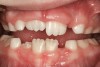

The point of obstruction tends to determine the type of skeletal impact. Nasal obstruction from enlarged turbinates, blocked ostium maxillare, deviated septum, or nasal valve stenosis creates Angle occlusions of Class I, II, and III equally (Figure 8). The maxilla in these cases is positioned posteriorly and the mandible is posterior-inferior. The facial type is most commonly dolicocephalic. Blockage of the airway predominately by the adenoids will create growth patterns that yield mostly Class II occlusions and anterior open bite with both jaws located posterior-inferiorly. Facial type is again dolicocephalic with the typical long-thin “adenoidal” face49 (Figure 9 through Figure 12). If the tonsillar tissue is responsible for the airway obstruction, the tongue will have an abnormal resting posture. Class III occlusions will be more common with the maxilla normal or posterior placed (Figure 13 through 15). The tongue may direct the mandible anteriorly or, because the tongue is not in the roof of the mouth driving A point anterior, the maxilla will become bimaxillary retrusive.50 In some cases, the anterior posture of the tongue will create an open bite. This is incorrectly referred to as a tongue thrust. The impact from a thrust does not alter the tooth position. Long-term, low forces cause tooth movement. The posture of the tongue against or between the anterior teeth due to the excessive tonsillar size creates the open bite (Figure 16 and Figure 17). Facial types in this group are more brachyfacial. Lastly, if the airway is blocked through a combination of factors, the Angle classification will be either Class II or III. The maxilla will be in a normal location and the mandible will be the affected arch (Figure 18). These craniofacial changes are not restricted to OSA; all SDB will create unique alterations depending on the patient compensation. Children with UARS have been reported to display high, narrow palates, dolicofacial form, and a Class II malocclusion, indicative of largely adenoidal blockage.51

(16.) Tongues with poor tone and posture may move the teeth over time and open the bite (Case courtesy of James Awbrey, DMD).

Figure 16